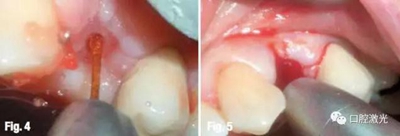

通過測量,種植的安全深度為12mm。選擇波長為2780nm水激光(Er,Cr:YSGG),在浸潤局部麻醉后,利用Z4/14激光工作尖在24中心處進(jìn)行切割氣化。激光設(shè)置為功率3W、脈沖能量150mJ、50%水、50%氣。激光發(fā)射方向由臨近牙齒和骨的形態(tài)決定。